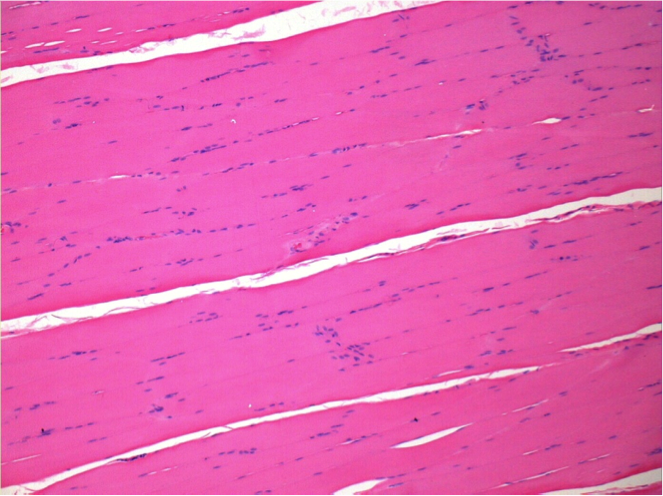

L:Pretibial-No treatment

10 days after Endopeel Injection 0.1ml in the right pretibial muscle.

Here you may see the formation of the vacuoles which are surrounded by lymphocytes. Vacuoles are different from tissue necrosis . The presence of lymphocytes is related to the permeability of the cell membranes.